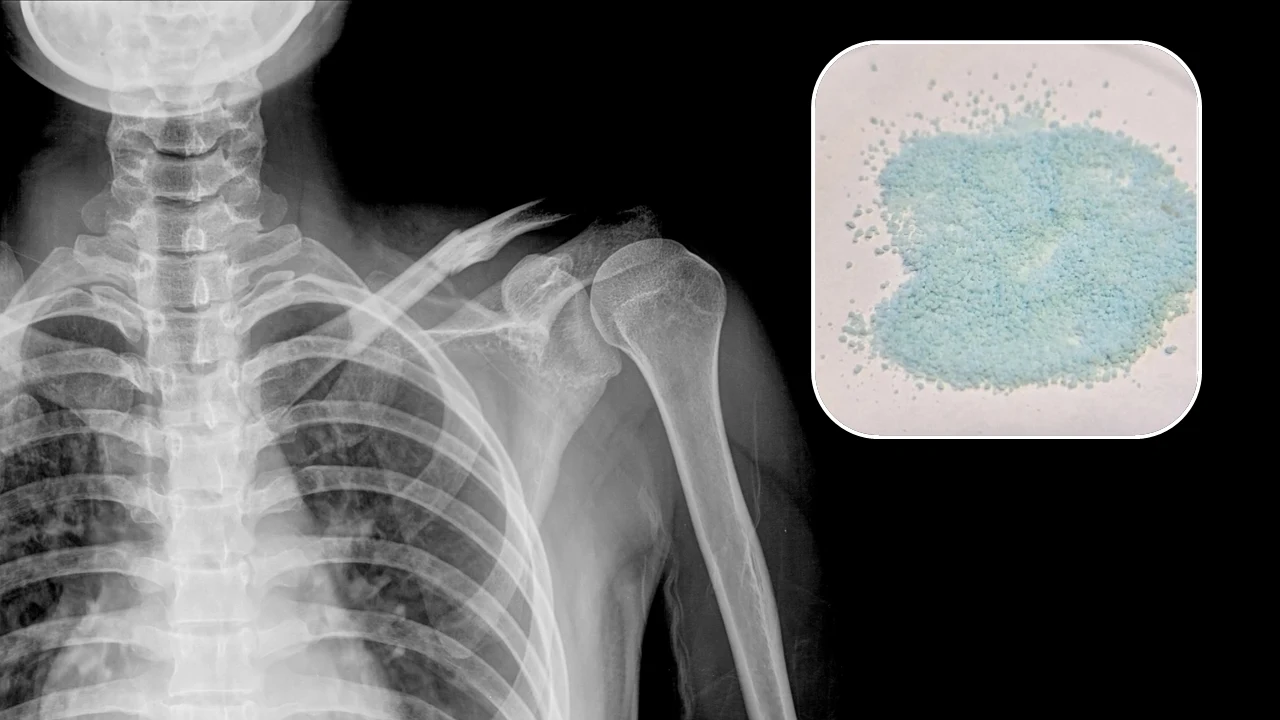

Wytworzone granule są na tyle duże, że widać je gołym okiem. Ich rozmiary sięgają od 100 mikrometrów (0,1 mm, niewiele więcej od średnicy ludzkiego włosa), do 1 milimetra. Najczęściej wykorzystywane są granule w zakresie 0,3-0,4 milimetra, ale naukowcy nie wykluczają stosowanie również innych rozmiarów.

Innym sposobem wykorzystania jest zastąpienie ubytków kostnych, zwłaszcza tych po wypadkach, które niemal zawsze mają nieregularny kształt. Aby je wypełnić, niezbędny jest materiał, który można łatwo formować i dostosować do kształtu ubytku.